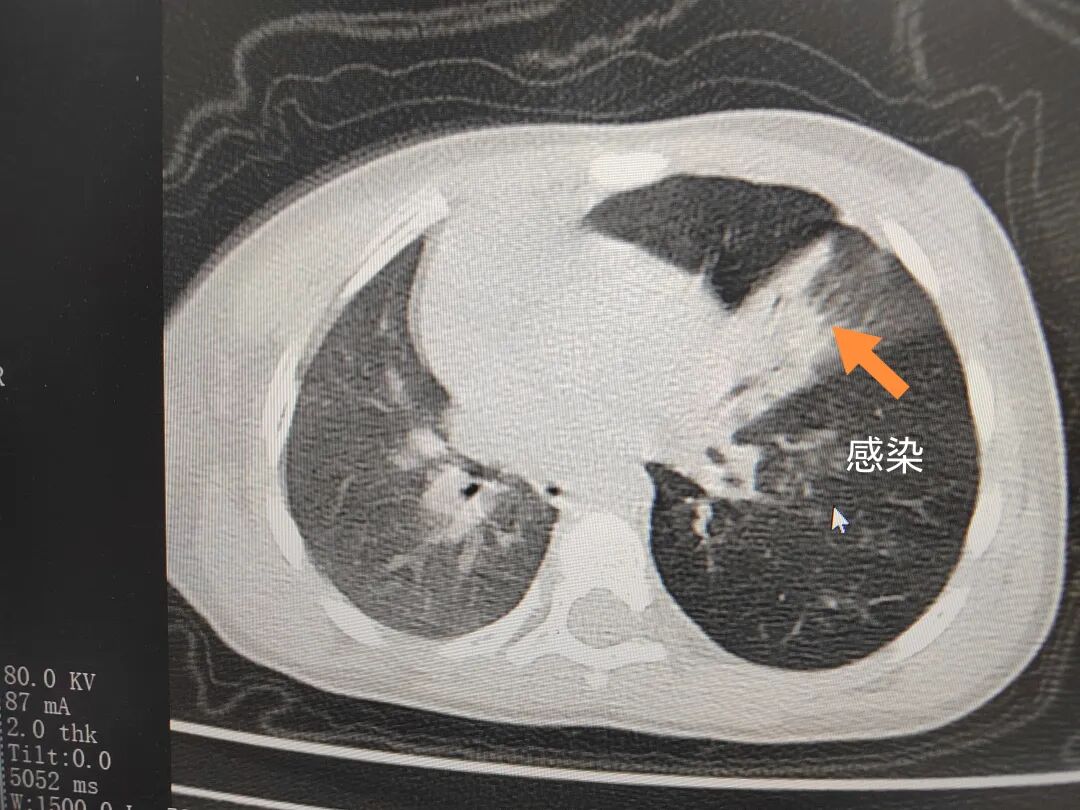

三天后(11月13日),趙寶出現(xiàn)高熱、咳喘加重,家長(zhǎng)著急了,再次帶他來(lái)到醫(yī)院。CT檢查顯示左肺過(guò)度充氣,左肺上下葉支氣管主干見(jiàn)不規(guī)則高密度影,左肺上葉可見(jiàn)大片狀密度增高影,縱隔窗實(shí)變,提示為“左側(cè)支氣管內(nèi)異物并繼發(fā)性改變,左肺上葉舌段肺膨脹不全”。